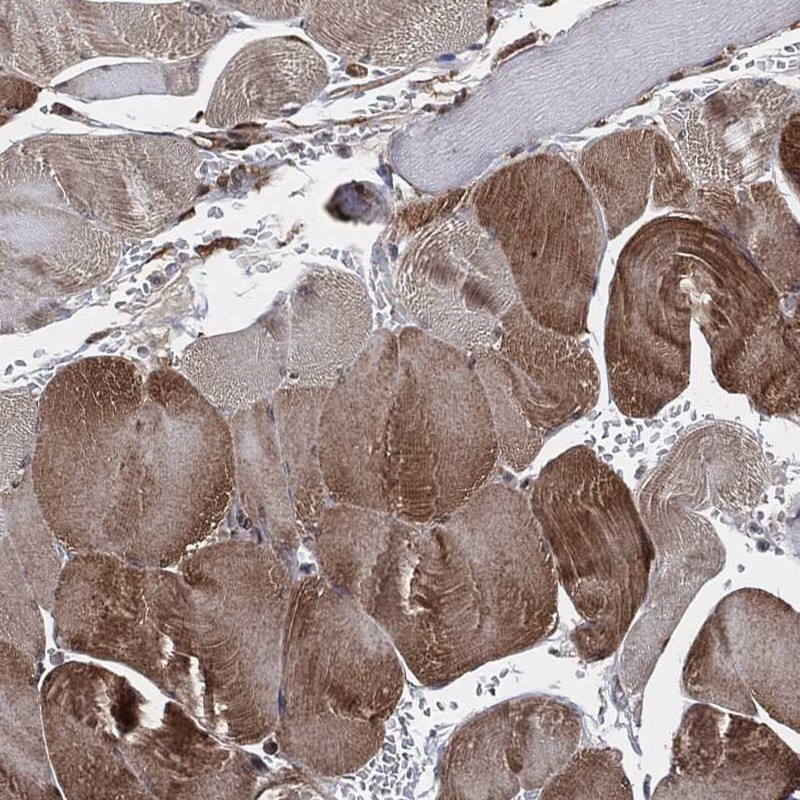

Immunohistochemical staining of human skeletal muscle shows moderate cytoplasmic positivity in myocytes.